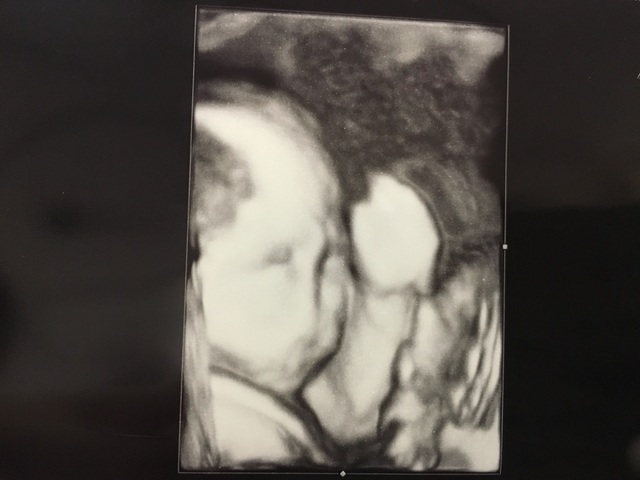

25週(25w・男の子)|takana さん(29歳)

エコー写真撮影時のエピソード:

検診の際いつも手で顔を隠していてはっきりと顔をみせてくれないのですが、初めてパパと4Dエコーを体験した時にタイミング良く赤ちゃんが微笑んでいる時の最高の一枚です。

エコーをしたくれていた院長先生も笑ってるねぇと言いながら写真とデーターを頂きました。